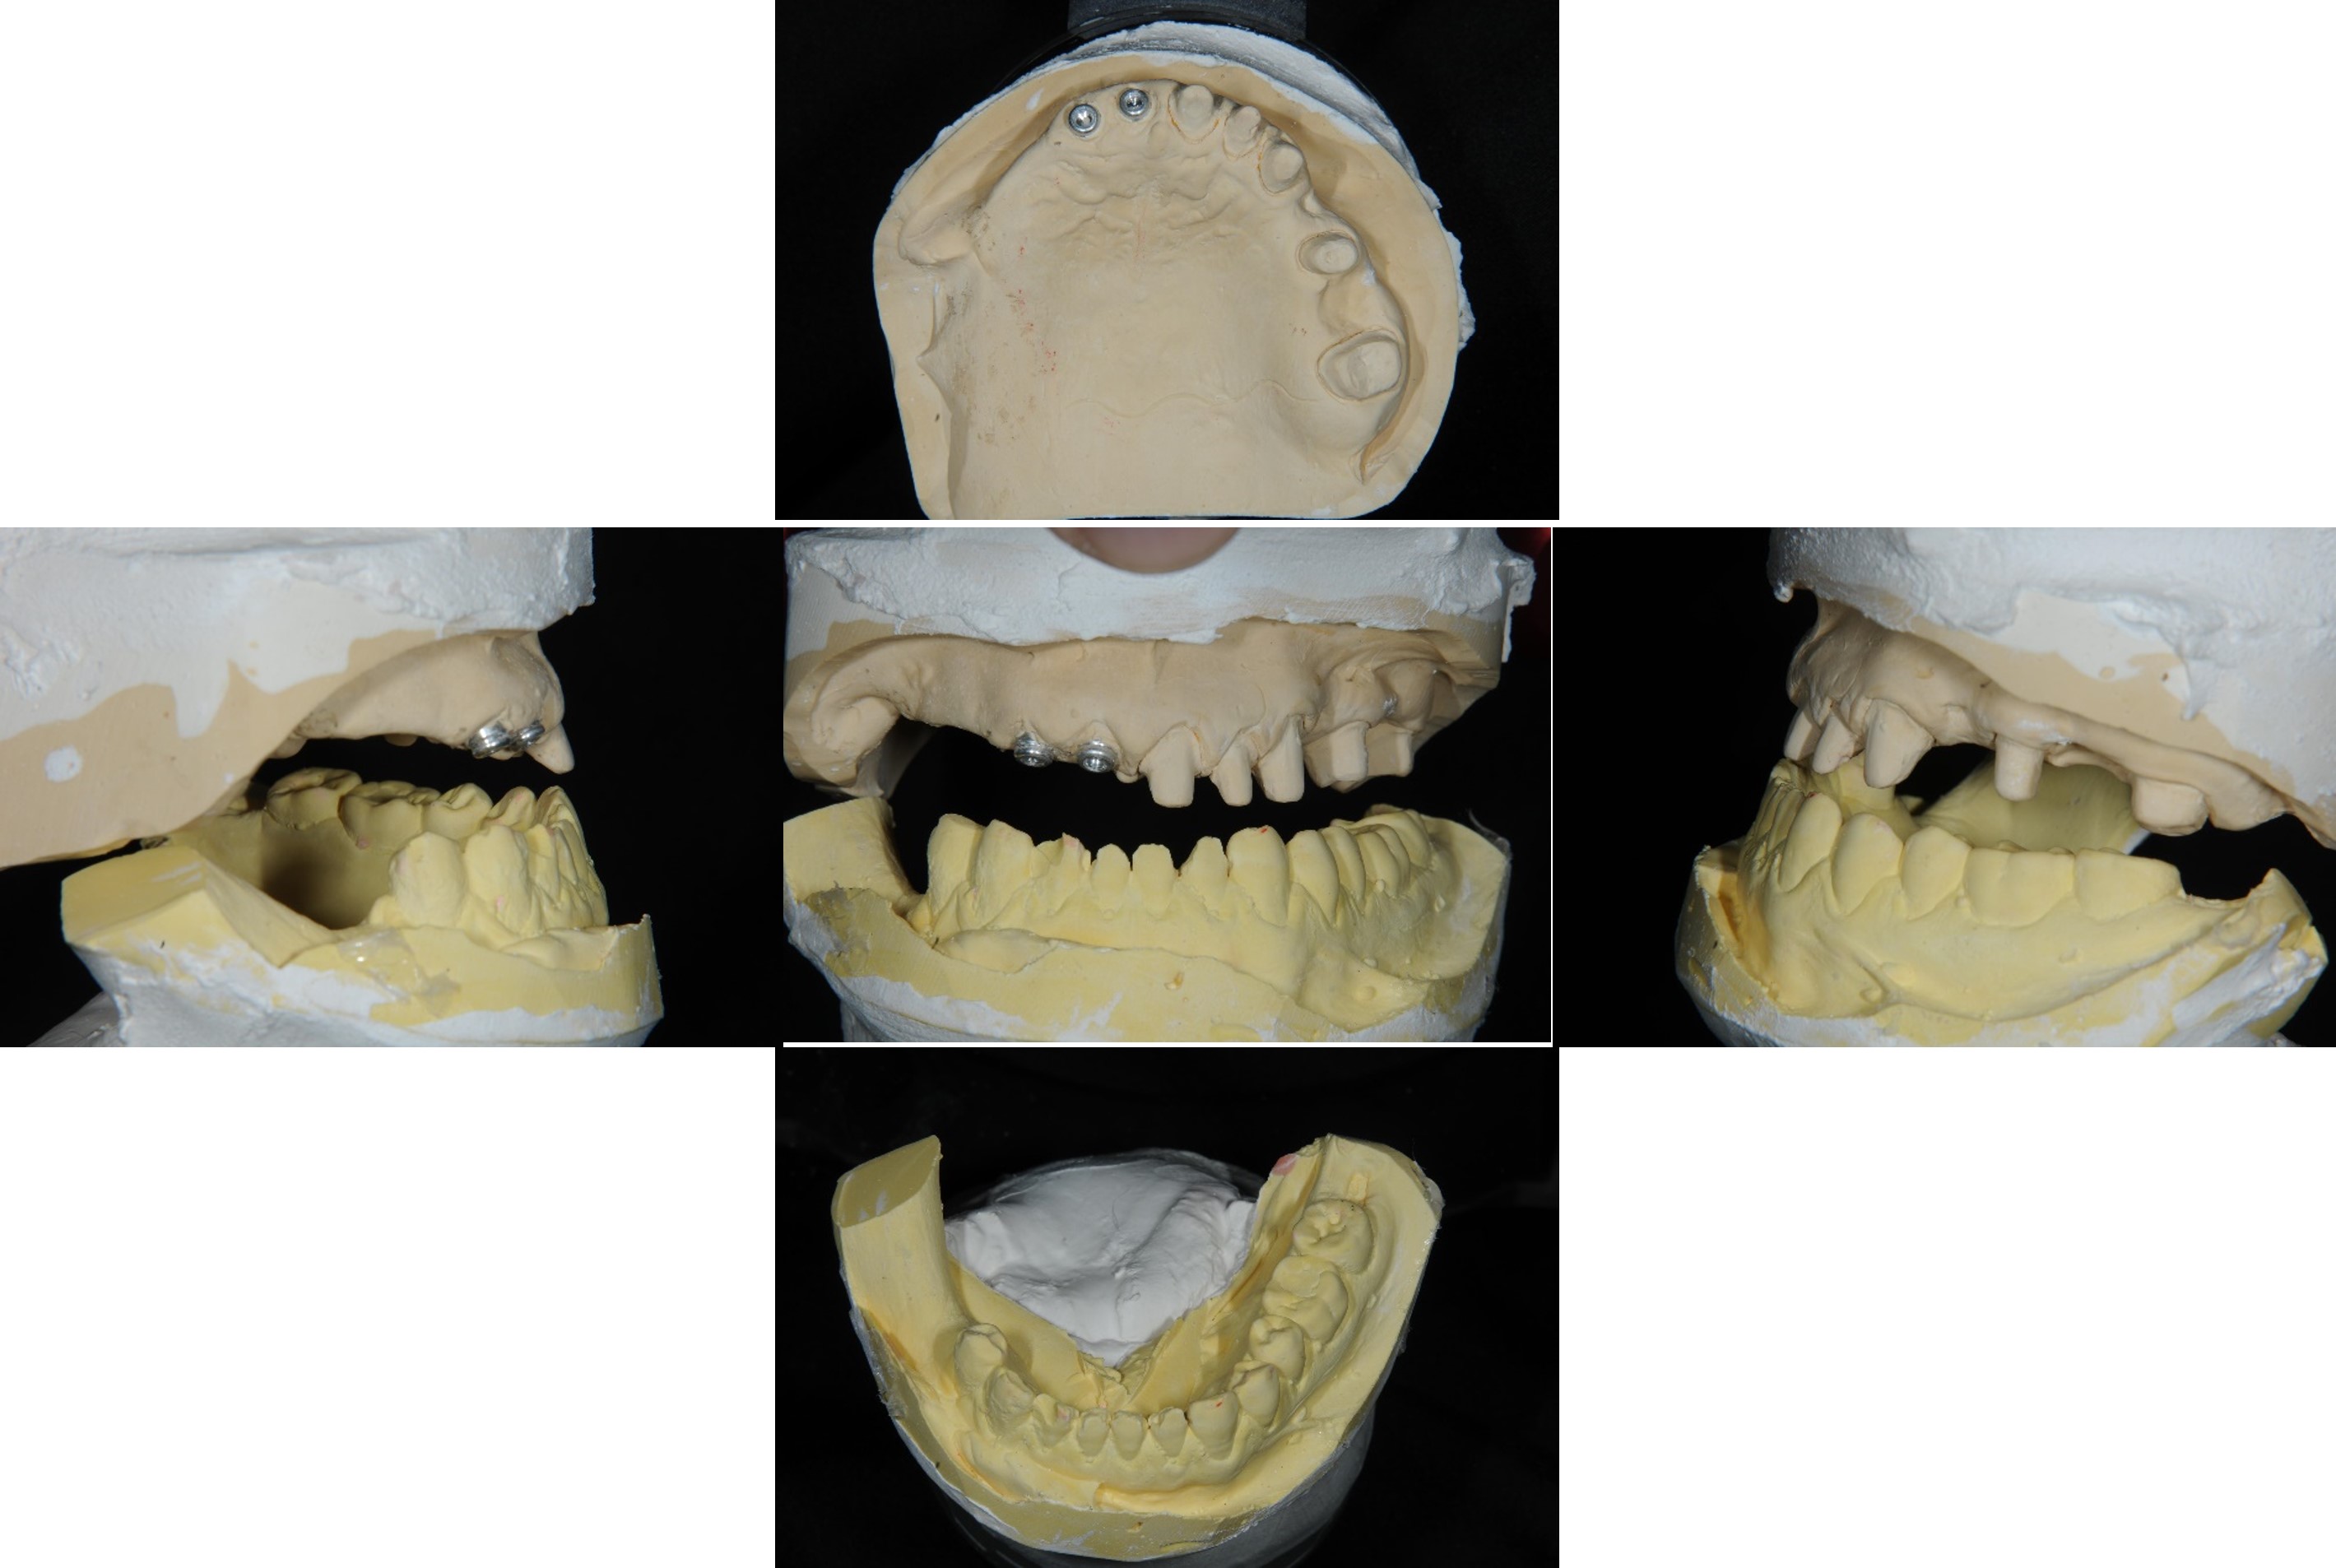

上下顎初步印模

模型咬合分析